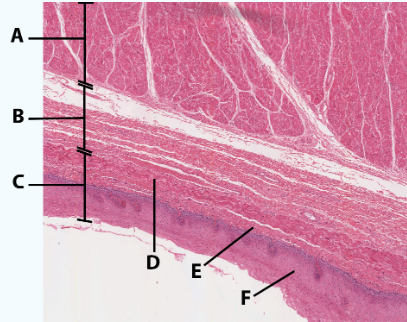

A

Serosa

B Esophagus

Muscularis externa: skeletal, skeletal/smooth, and smooth, circular and longitudinal

C

Submucosa: areolar and dense connective tissue

D

Lumen

A

Muscularis

B

Submucosa

C

Mucosa

D

Muscularis mucosa

E

lamina propria

F

stratified squamous epithelial tissue

area

Esophagus